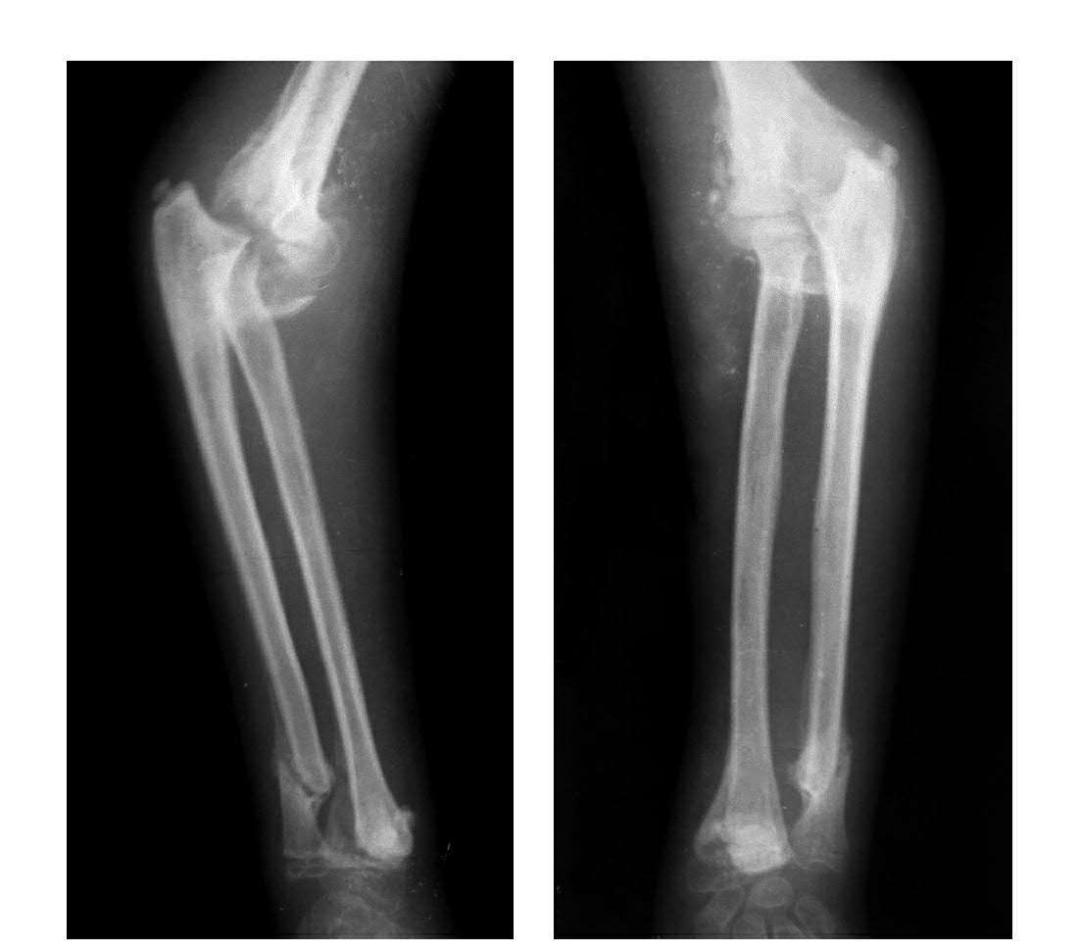

肘关节爆裂性脱位

本病亦称三关节脱位。

例1:肘关节内外型爆裂性脱位(即肘关节后脱位并上尺桡关节向内外侧分离)。

例2:肘关节前后型爆裂性脱位(即桡骨脱向肘前上,尺骨脱向肘后上)。

例3:其主要病变同例1并同侧桡骨远端骨骺滑脱。